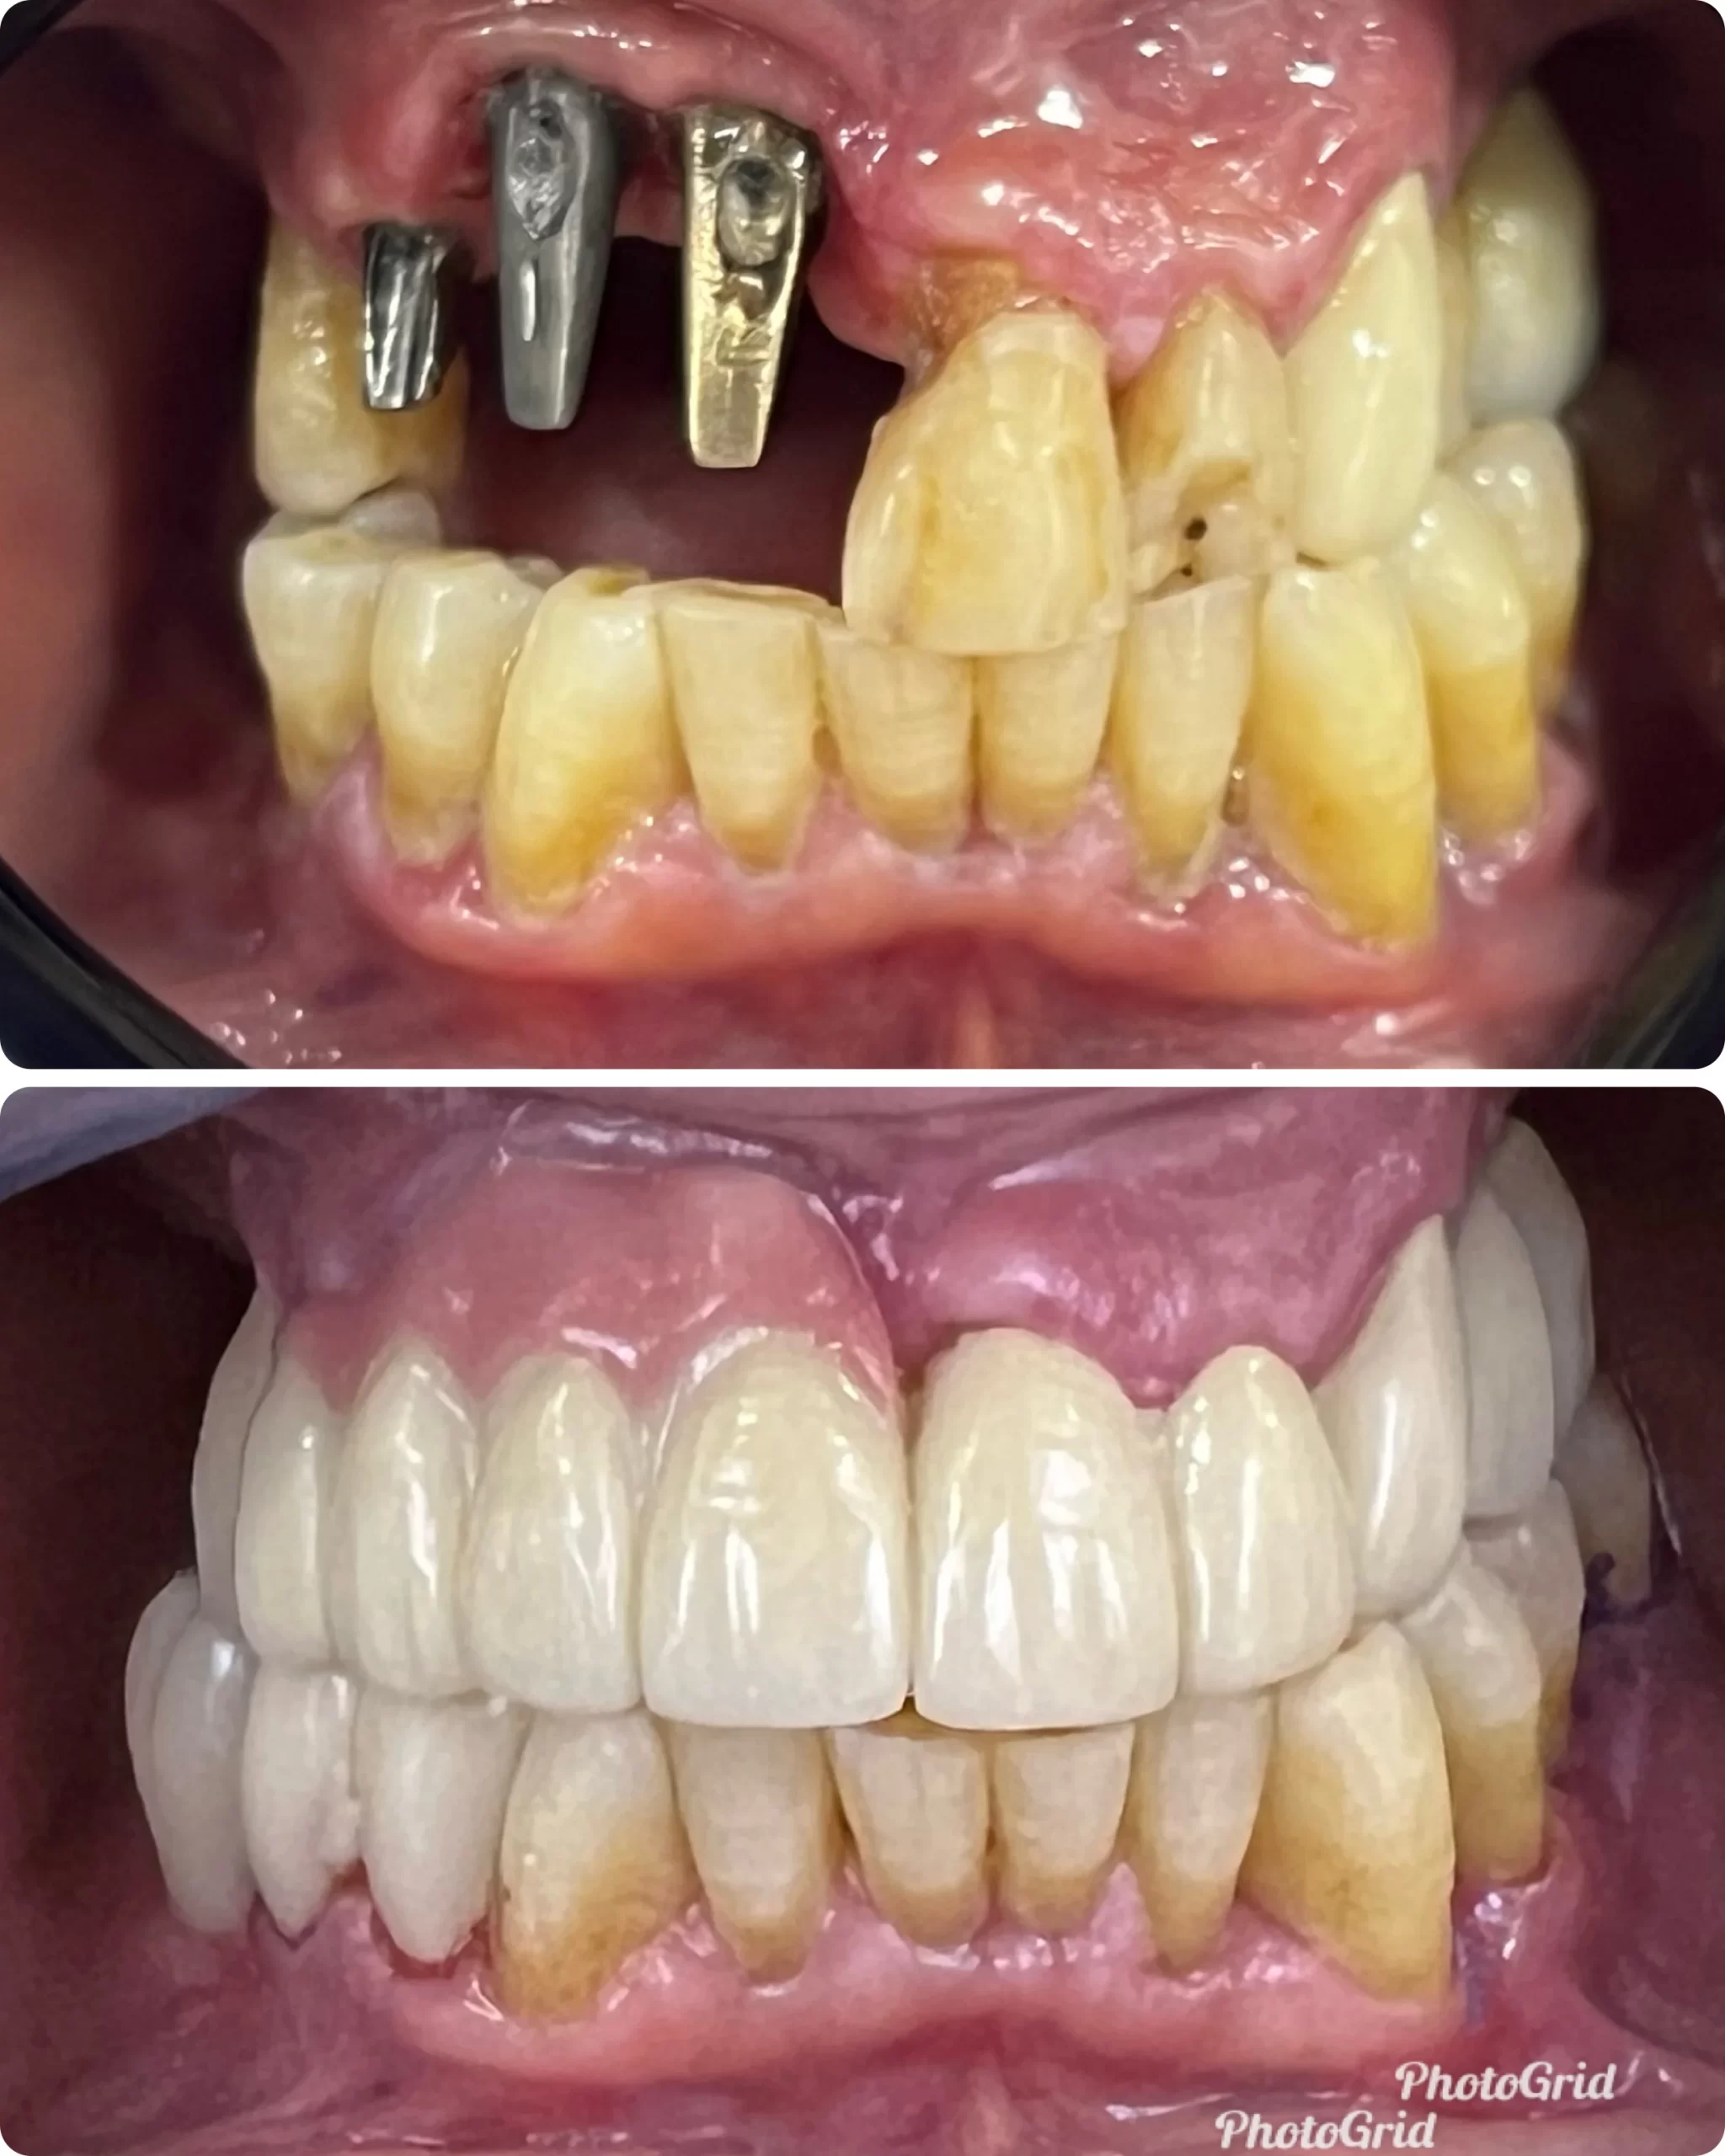

Dental implants consist of three key parts- the fixture, the abutment, and the dental prosthesis. These components mimic natural teeth, preventing bone loss and averting the shifting of adjacent teeth. By filling in gaps, implants safeguard your smile and prevent further tooth loss.

Beyond physical health benefits, dental implants significantly enhance self-confidence. Implants provide a natural-looking, secure solution that restores your appearance and improves speech clarity. Unlike dentures, implants stay firmly in place, eliminating concerns about slipping or discomfort.

Showing Our Expertise In Dental Implantology